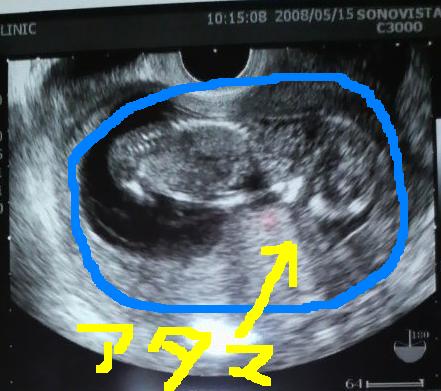

んで、今日はジロー初公開!

とくと見よ!これがジローのビフォーアフター!!

◆ジロー4/19 → 5/19

Do-よコレ(・∀・)!!

でっかくなったでしょ?

小指代だったのがこんなに大きくなりました。

これ写した時は足を曲げて足首を交差させてる状態だったですよ。残念ながらまだ性別は分からず・・・次で判明するといいなー。ベビー服早く買いたいYO(*´Д`)ハァハァ

とりあえず、今こんだけ大きければ超順調という事らしいので嬉しい限り。